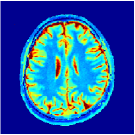

Two sets of experiments were conducted here: first, we used the 2D and 3D acquisition sequences for scanning a healthy volunteer’s brain (real-world acquisitions). Figures 6 and 7 display the parametric maps reconstructed from 2D spiral and radial readouts. We computed the T1, T2 and proton density (PD) maps using baseline reconstruction algorithms ZF, VS, LR, FLOR, AIR-MRF and our proposed LRTV. While baselines use DM either for quantitative inference or also during reconstruction (i.e. AIR-MRF), we further compare the DM-free LRTV’s performance when cascaded to DM, KM and MRFResnet for quantitative inference. For the 3D spiral acquisitions we compared LRTV and its closest competitor VS in Figure 8. Outcomes from other tested algorithm are displayed in the supplementary materials (Figure S5). Since FLOR does not use dimensionality-reduction, our system ran out of memory during 3D reconstruction; hence results are not reported in this case.

VI-E1 Discussion

The LRTV-DM and LRTV-MRFResnet perform on par, and both outperform all tested baselines for reconstructing T1, T2 and PD maps in all acquisition schemes. This can be observed both visually in Figures 6, 7, 8, S2 and S3, and quantitatively in Table IV across all tested metrics. Other baselines were unable to successfully remove the under-sampling artefacts in TSMIs, and these errors propagated to the parameter inference phase and resulted in inaccurate maps. Temporal-only priors incorporated within LR are shown insufficient to regularise the inverse problem and LR sometimes (e.g. 2D spiral acquisitions) can admit solutions with even stronger artefacts than the model-free ZF baseline. This issue was previously studied for other non-Cartesian MRF readouts that similar to our spiral/radial trajectories, miss to sample the corners of the k-space in all timeframes (see section 2.2.2 and figure 2 in [19]). In the absence of reference for the k-space corners information, the LR iterations despite minimising the objective can converge to solutions with high-frequency artefacts, as visible in the computed maps. This highlights the need for adding an appropriate spatial-domain regularisation. FLOR reduces the LR’s artefacts but this improvement is limited because the suggested nuclear norm penalty does not incorporate an explicit spatial regularisation. Further for reducing artefacts, FLOR can introduce an undesirable bias in the computed T1/T2 maps e.g. see error maps in Figures S2 and S3. The non model-based VS baseline incorporates spatial regularisation and results in spatially smoother maps than ZF and LR, but it is unable to output artefact-free images. Further and consistent with our in-vitro experiment, we observe that VS overestimates the T2 values (e.g. in White and Grey matter regions) in tested 2D acquisitions i.e. the spatial regularisation trades off agains the quantification accuracy. The model-based AIR-MRF adds spatial regularisation through 2D/3D low-pass Gaussian filters however this trades off the sharpness of the computed maps and can increase the errors at the tissue boundaries (we searched Gaussian spreads that keep the blurs and high-frequency artefacts minimal). For our acquisition readouts, Gaussian filters performed better than disk filters of [19] for avoiding strong Gibbs artefacts. On the other hand, the spatiotemporally regularised LRTV greatly improves the TSMI reconstructions i.e. 4 dB enhancement compared to the closest competitor baseline (Table IV). This enables computing accurate and aliased-free multi-parametric inference using DM or the DM-free learning-based alternative MRFResnet as visible in Figures 6, 7, 8, S2 and S3. MRResnet and DM score competitive quantitative inference results i.e. T1 and T2 MAPE less than 5% and 9%, respectively (Table IV). KM also outputs comparably accurate T1 maps, however this shallow learning model despite having a model size larger than MRFResnet, is unable to learn accurate T2/PD quantification and it results in poor estimated maps, consistent with our observations in section VI-C.